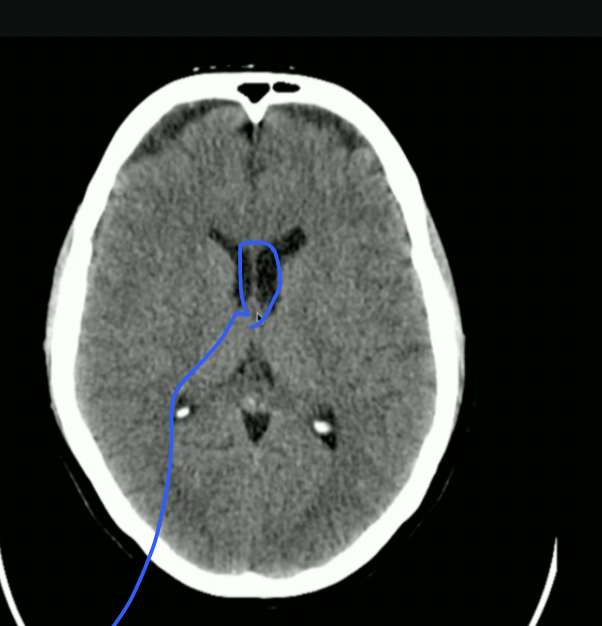

<p>What is highlighted?</p>

What is highlighted?

• 3rd Ventricle

• CSF then goes to Cerebral Aqueduct